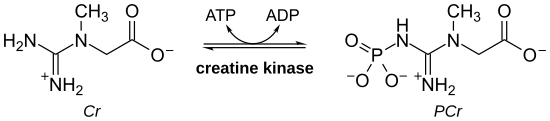

- CDG I (DPM3) some of the symptoms at birth and throughout the infant's life are weakness or poor muscle tone. The individual may present with cardiomyopathy (no outflow obstruction), a rise in serum creatine kinase might be present as well. Some IQ problems may be present, along with weakness in the proximal muscles. Also of note, a reduction of dolichol phosphate mannose .[23]

- Integrin α7 weakness which is present at birth, poor muscle tone with late walking, loss of muscle tissue, intellectual disability.Furthermore, the creatine kinase level was elevated.[28]